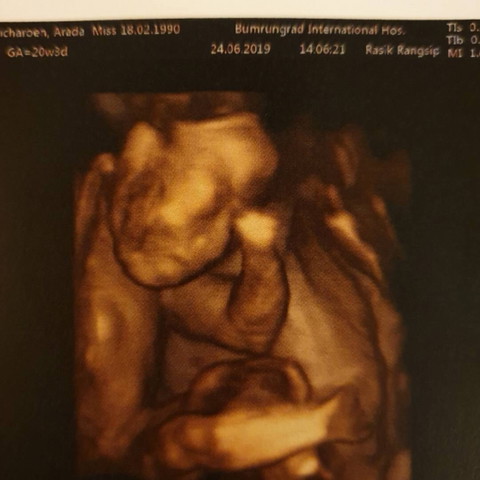

ตอน 5 เดือนค่า 😁

ผู้ชายค่ะ